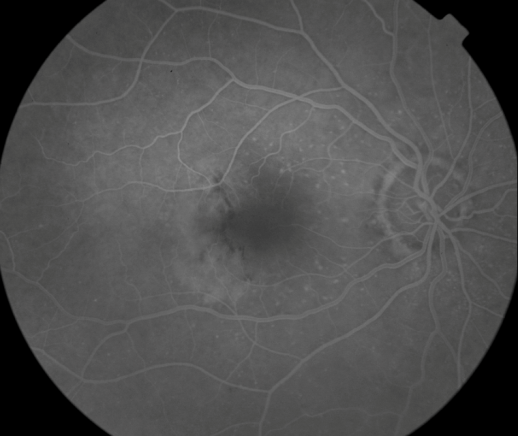

OD Red-Free: Pre-Injection: Arterial: A-V: Venous: Recirculation: Late:

OS Red-Free: Venous: Recirc: Late:

Impression